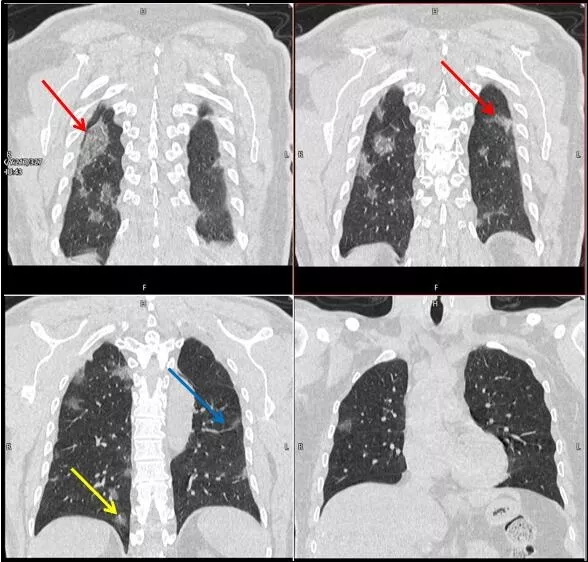

武漢大學(xué)中南醫(yī)院影像科副主任張笑春教授發(fā)現(xiàn),目前武漢市家庭聚集性發(fā)病較多,而且大多起病隱匿,一次甚至多次核酸陰性,無任何臨床癥狀,CT檢查卻已顯示為病毒性肺炎特征。

為了盡快篩查新型冠狀病毒肺炎患者,醫(yī)院會(huì)選擇影像診斷作為早期發(fā)現(xiàn)新型冠狀病毒感染的肺炎的重要一環(huán)。

CT為當(dāng)前首選篩查與診斷的主要影像學(xué)手段,胸部CT的病毒性肺炎檢出率高。

方舟CT(CT Ark)可以滿足全面的臨床功能,配置16層、32層、64層、128層CT,實(shí)現(xiàn)了低劑量掃描要求,配合NDI微劑量迭代技術(shù),智能毫安調(diào)控技術(shù),使各種場(chǎng)合下、各部位低劑量掃描得以實(shí)現(xiàn);超高分辨率CT病灶靶掃描,使病灶的密度顯示更加精確,能夠顯示病灶內(nèi)輕度的密度變化,有利于小病灶的密度定量分析和及時(shí)診斷。